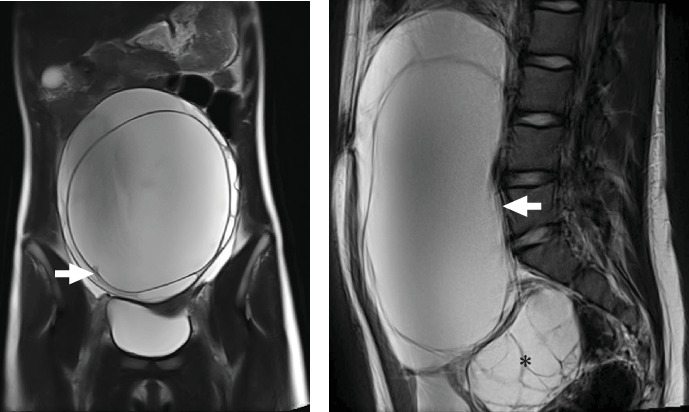

Objective: To present a rare diagnosis of polycystic ovary syndrome (PCOS) after initial suspicion of malignancy. PCOS is a common endocrine disorder in adolescence characterized by hyperandrogenism and polycystic ovaries. Case Presentation: A 13-year-old female patient was referred for a giant mass noted on examination for metrorrhagia. She had previously presented for hirsutism and acne, treated independently. A multicystic abdominal tumor measuring 21 × 17 × 9 cm was identified, with a nodular image and negative tumor markers, but elevated testosterone and LH/FSH ratio. Therefore, video-assisted ovarian cystectomy was performed. Finally, the patient was diagnosed with PCOS and began hormonal therapy, with improvement of hyperandrogenism. Conclusion: In adolescents with large ovarian cysts, in addition to ruling out malignant neoplasms, PCOS should be considered as these may have similar clinical and radiological presentations.